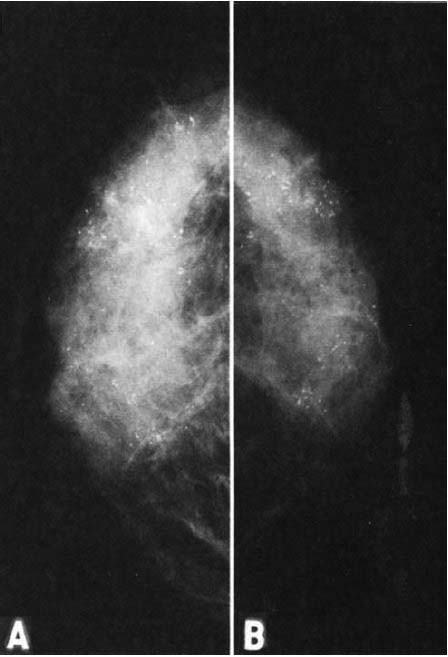

図11.A:片面乳剤+増感紙の新システム.B:増感紙を使用しない従来のシステム.微細石灰化がより明瞭で,組織全体の鮮鋭度,コントラストにも優れている.

【要旨・解説】通常のX線写真は両面乳剤フィルムを2枚の増感紙ではさんで撮影するのが一般的であるが,高空間分解能,高濃度分解能が要求されるマンモグラフィーは,粒状性に優れた低速の工業用X線フィルムを使用し,かつ増感紙なしで撮影するのが一般的であった.しかし,曝射時間が長く,被曝線量が大きいことが問題となる.

本稿は,1973年にDu Pont社が開発した片面乳剤と高精細増感紙を組合わせたシステムの報告である. フィルムは比較的低速の片面乳剤で,両面乳剤におけるクロスオーバー露光の問題も回避できる.さらにフィルムと増感紙を真空装置を利用して密着させるなどの工夫を重ねて,高解像度,低線量システムの開発に成功した(図11).被曝線量は,従来の無増感紙方式にくらべて1/8に低減した. このシステムはその後Lo-doseの商品名で市販され,その後デジタルマンモグラフィーに置換されるまで,フィルムマンモグラフィーの標準的な撮影方法となった.